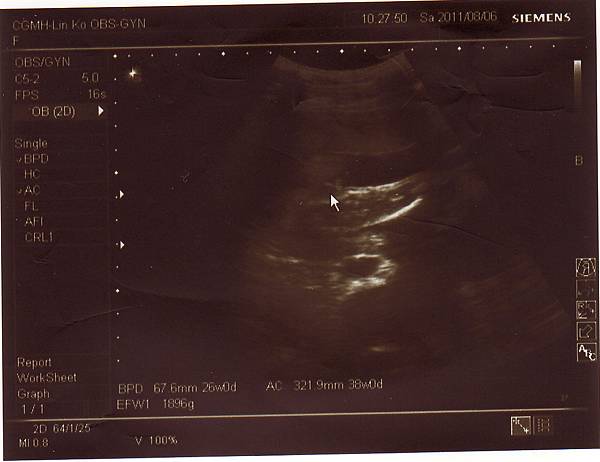

2011.08.06 26週 例行性產檢

終於今天產檢,問了醫生寶寶大小,

醫生說大約九百多克,和同期的寶寶比起來重量也不輕,

而兔妹妹的發展也符合懷孕週數,